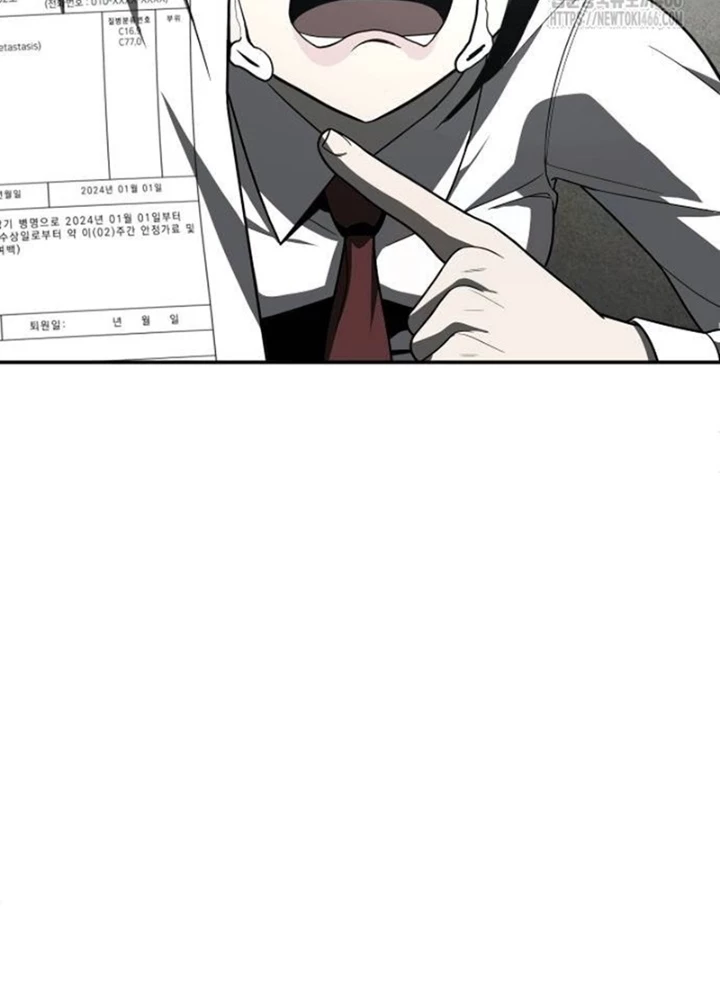

Món Đồ Chơi - Chapter 43